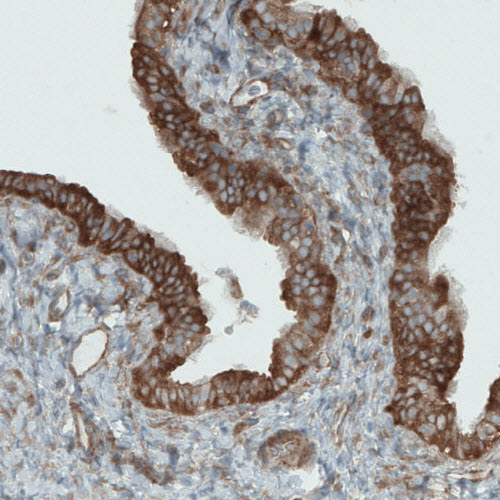

Product information "Anti-DIAPH2, clone CL1111"

Protein function: Could be involved in oogenesis. Involved in the regulation of endosome dynamics. Implicated in a novel signal transduction pathway, in which isoform 3 and CSK are sequentially activated by RHOD to regulate the motility of early endosomes through interactions with the actin cytoskeleton. [The UniProt Consortium] Validated by genetic and standard strategies. Buffer: 40% glycerol and PBS (pH 7.2). 0.02% sodium azide is added as preservative. Highest antigen sequence identity to mouse: 82% and to rat: 33%. Epitope specificity: SLNLSEKEVLDLFEK.

| Application: | IHC, WB |